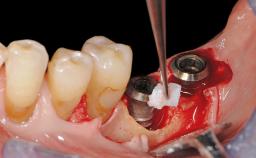

Treatment of Advanced Peri-Implantitis by Implant Removal Followed by Bone Reconstruction and New Implant Placement

Paolo Casentini and Matteo Chiapasco present a case in which the peri-implant defect was not suitable for a fully regenerative approach. It involves implant removal, use of a CAD/CAM customized titanium mesh in the grafting phase, and placement of new implants. A 62-year-old woman was referred for consultation regarding her implant-supported prosthesis replacing teeth 14 to 16. The patient’s main concern was pain and recurrent swelling in the right posterior maxilla. The patient also reported difficulty and discomfort when brushing the area. The patient reported she had been treated in another country, where she had received three implants in combination with sinus-floor augmentation for the replacement of the posterior maxillary teeth three years earlier. The patient indicated “endodontic complications” to be the reason for the extraction of the teeth.